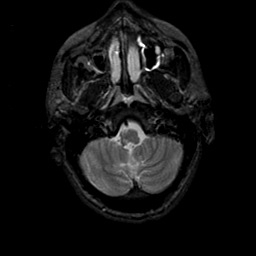

MR Study #23, January 26, 1992 -- Slice #7